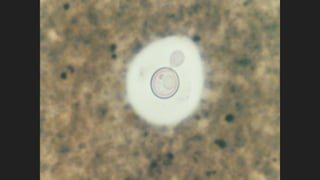

C. neoformans: Características Generales

Cápsula

diámetro celular: 2.5 µm a 10 µm

Brote

EXAMEN MICROSCOPICO:

Tinta China

Tinta China Modificada, JCM; 1996,

34(9):2290–2291

Material Fibrilar

Estrato Lúcido

Zona Clara